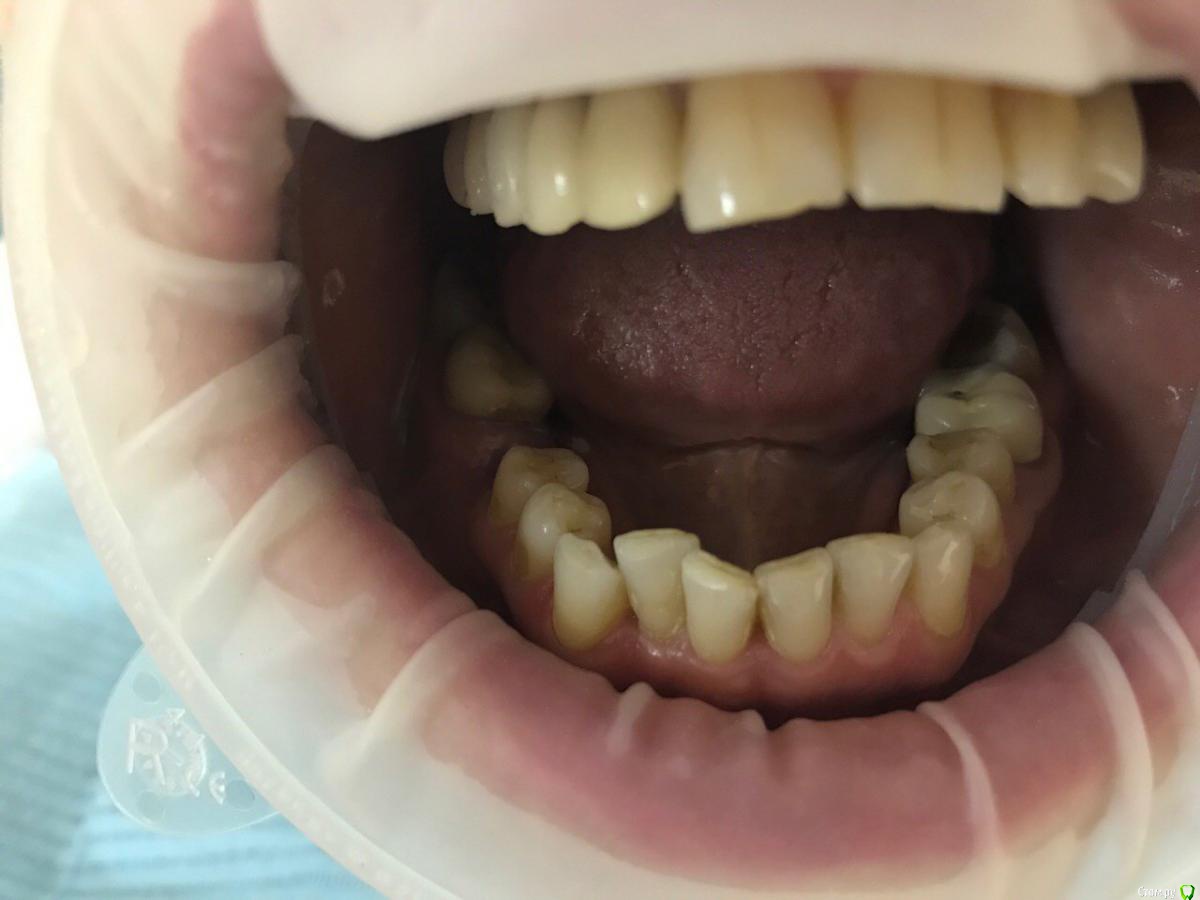

ksenistom Опубликовано 13 декабря, 2016 Поделиться Опубликовано 13 декабря, 2016 Пациентка И.,55 лет,хочет голливуд на обеих челюстях,в виде циркониевых коронок,справа сверху снят мостовидный протез,где установлены 2импл. неделю назад и удалён ретинированный клык в обл 13зуба(фото панорамы нет),поэтому эту сторону пока не трогаем,в области 46 планируется имплантация, 36зуб-вкладка+коронка,в области скученных нижних зубов сделан воксап.Вопрос в том,с чего начать?! Ссылка на комментарий

ksenistom Опубликовано 13 декабря, 2016 Автор Поделиться Опубликовано 13 декабря, 2016 План есть,я хочу начать слевой стороны,обточить верх и низ,навстречу друг другу,потом фронт и в последнюю очередь правую сторону,все под временные,оттиски,примерка каркасов,готовой работы и фиксация.От ортодонта отказалась из-за длительного лечения Ссылка на комментарий